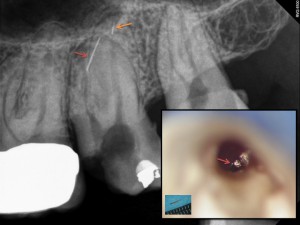

• Endodontische Zugangskavität